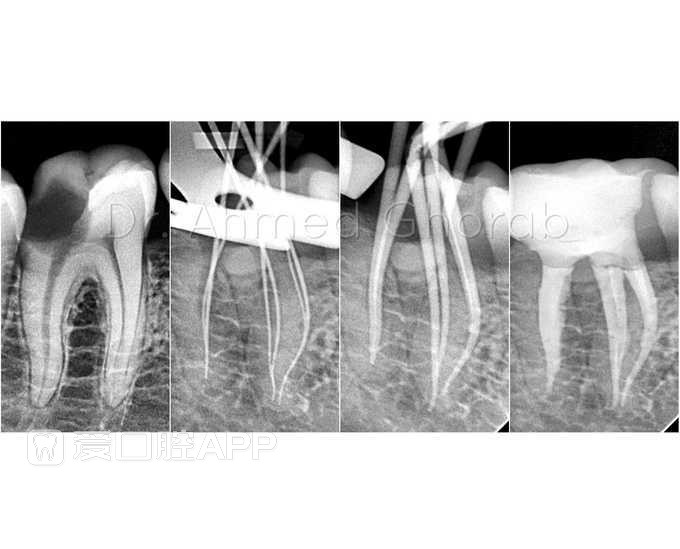

看个6个根管的治疗:下颌第一磨牙 by Dr Ahmed Ghorab

关于下领第一磨牙:髓室呈立方形,髓室顶形凹,最凹处约与颈缘平齐,近舌髓角与远舌髓角高度相近,两者均接近牙冠中 1/3 处。通常有3 个根管,即近中2个根管,远中1个根管。远中根管粗大呈椭圆形,有时亦可出现 2 个根管,近颊根管弯曲较明显。平均牙长为 21mm,冠根比例为1:1.72。侧支根管发生率为 30% 左右。